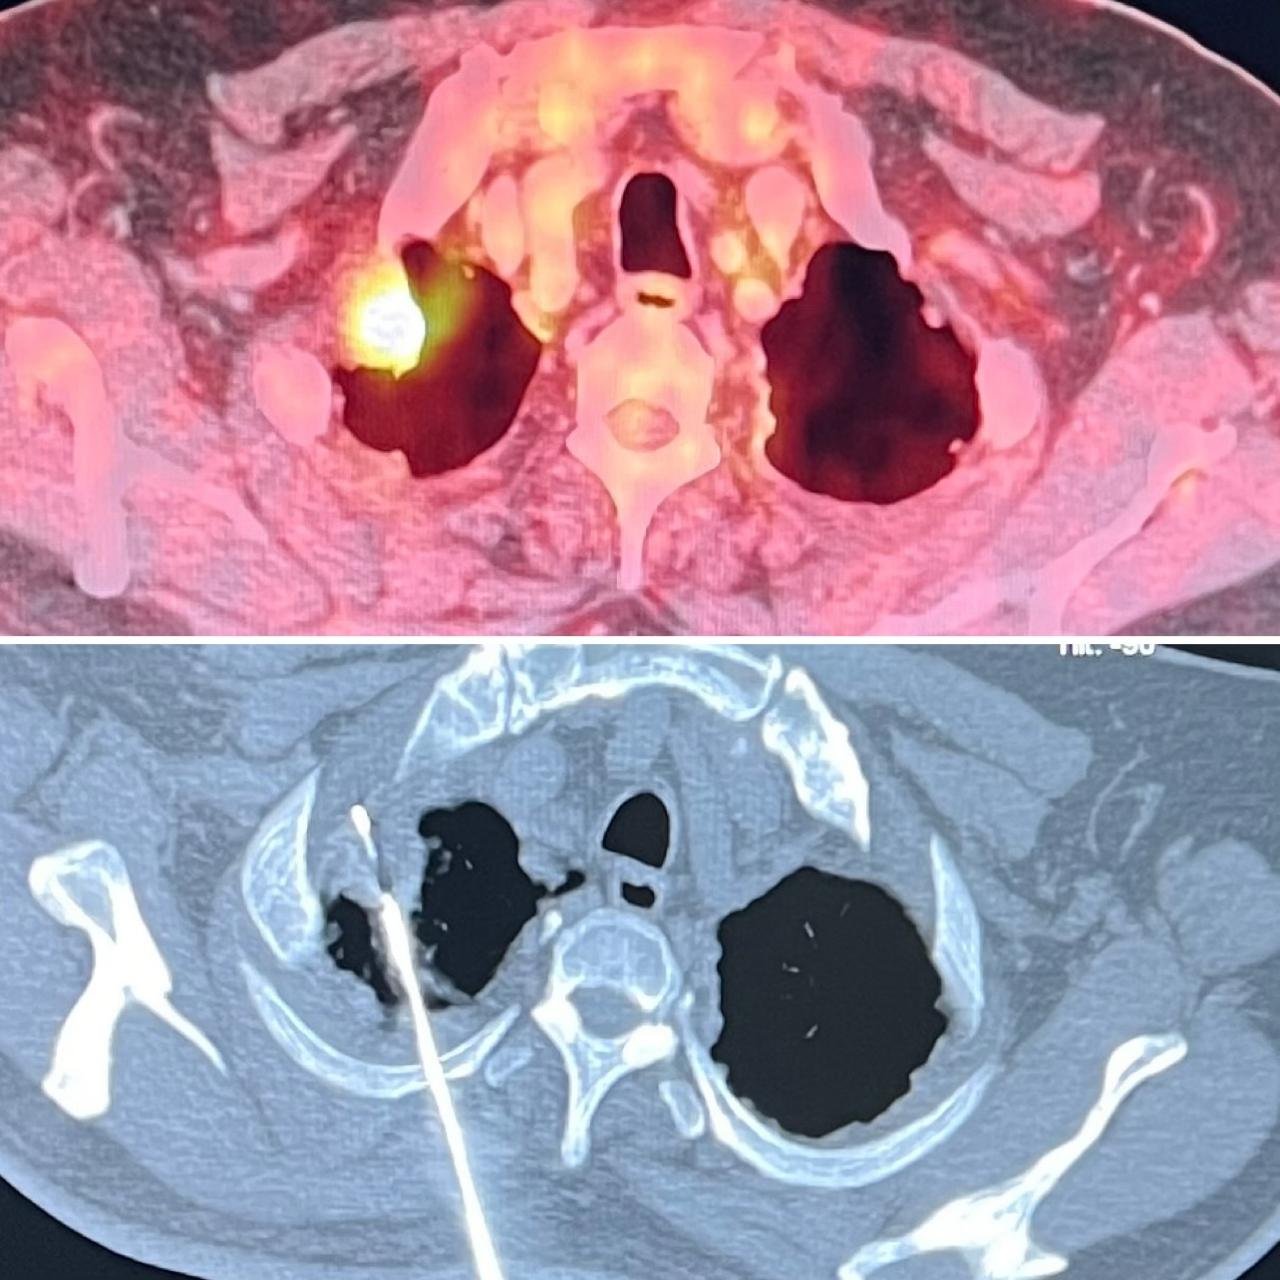

Oncological Interventions: TACE, TARE, Thermal Ablations, Liver Transplant Interventions

Neurovascular & Other Procedures: Osteoid Osteoma Ablations, Neurovascular Interventions